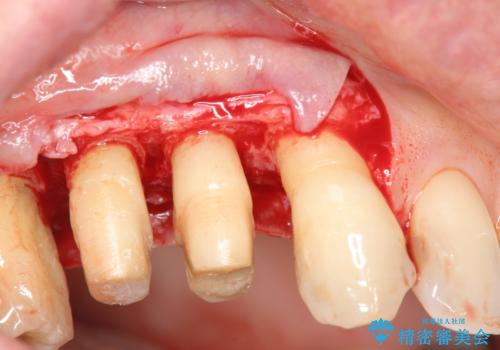

検査の結果、強い歯ぎしりによる歯の周囲の骨の吸収が認められたため歯槽骨の再生・歯周ポケットの除去・力に対抗する連結補綴・補綴前処置としての小矯正を計画します。

今回連結補綴を行うにあたり、歯周病の問題を解決するために再生療法・歯周ポケット除去手術を、またより歯の神経を保存し力に対抗できる環境を整えるために小矯正を行い精度の高いメタルボンドクラウンを製作することができました。